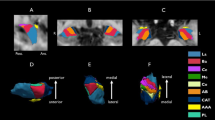

Network construction

A brain network can be described as a graph with nodes representing brain regions and edges that form connections between the nodes. The nodes were defined using the Automated Anatomical Labeling (AAL) atlas, which included a total of 116 cortical and subcortical regions. Motion-corrected DTI data was first reconstructed in the MNI space using q-space diffeomorphic reconstruction (QSDR) to obtain the spin distribution function. A diffusion sampling length ratio of 1.25 was used60. Whole-brain deterministic tractography was performed in DSI Studio (http://dsi-studio.labsolver.org). Fiber tracking was stopped if the reconstructed fiber entered a voxel with quantitative anisotropy (QA) of less than 0.2, and if the streamline made a turn with a curvature angle of more than 45 degrees. Tracts with length less than 30 mm were discarded. The overall pattern of WM connections between each pair of brain nodes was computed using weighted matrices. In the weighted matrices, each edge represented the product of the count of the connection tract. The connectivity matrices and graph theoretical analysis were conducted using the DSI Studio and Brain Connectivity Toolbox25. The following global network metrics were investigated: network density, clustering coefficient, small-worldness, global efficiency, local efficiency, and assortativity coefficient.

Network-based statistics (NBS)26 was used to further localise specific pairs of brain regions where WM structural connectivity was altered in hypos-PD patients. General linear models were used to examine the mean difference in connectivity strength (defined by QA) of any connected components between groups. A corrected p value was calculated for each component, using the null distribution of maximal connected component size derived with a nonparametric permutation method.